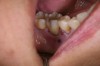

Fig 2. A PLGA alloplast bone grafting material was placed and molded to shape the area.

Figure 2